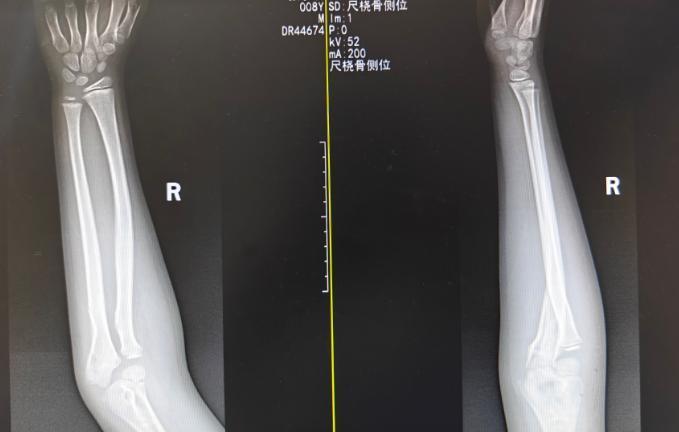

通过防止而精确的中医正骨手法,欺诈牵拉、挤压、屈伸等看成,使移位的骨撅断端“转头原位”。大夫“手摸心会,法从手出”。仅用时数分钟,复位完成,X光透视败露对位对线讲究。